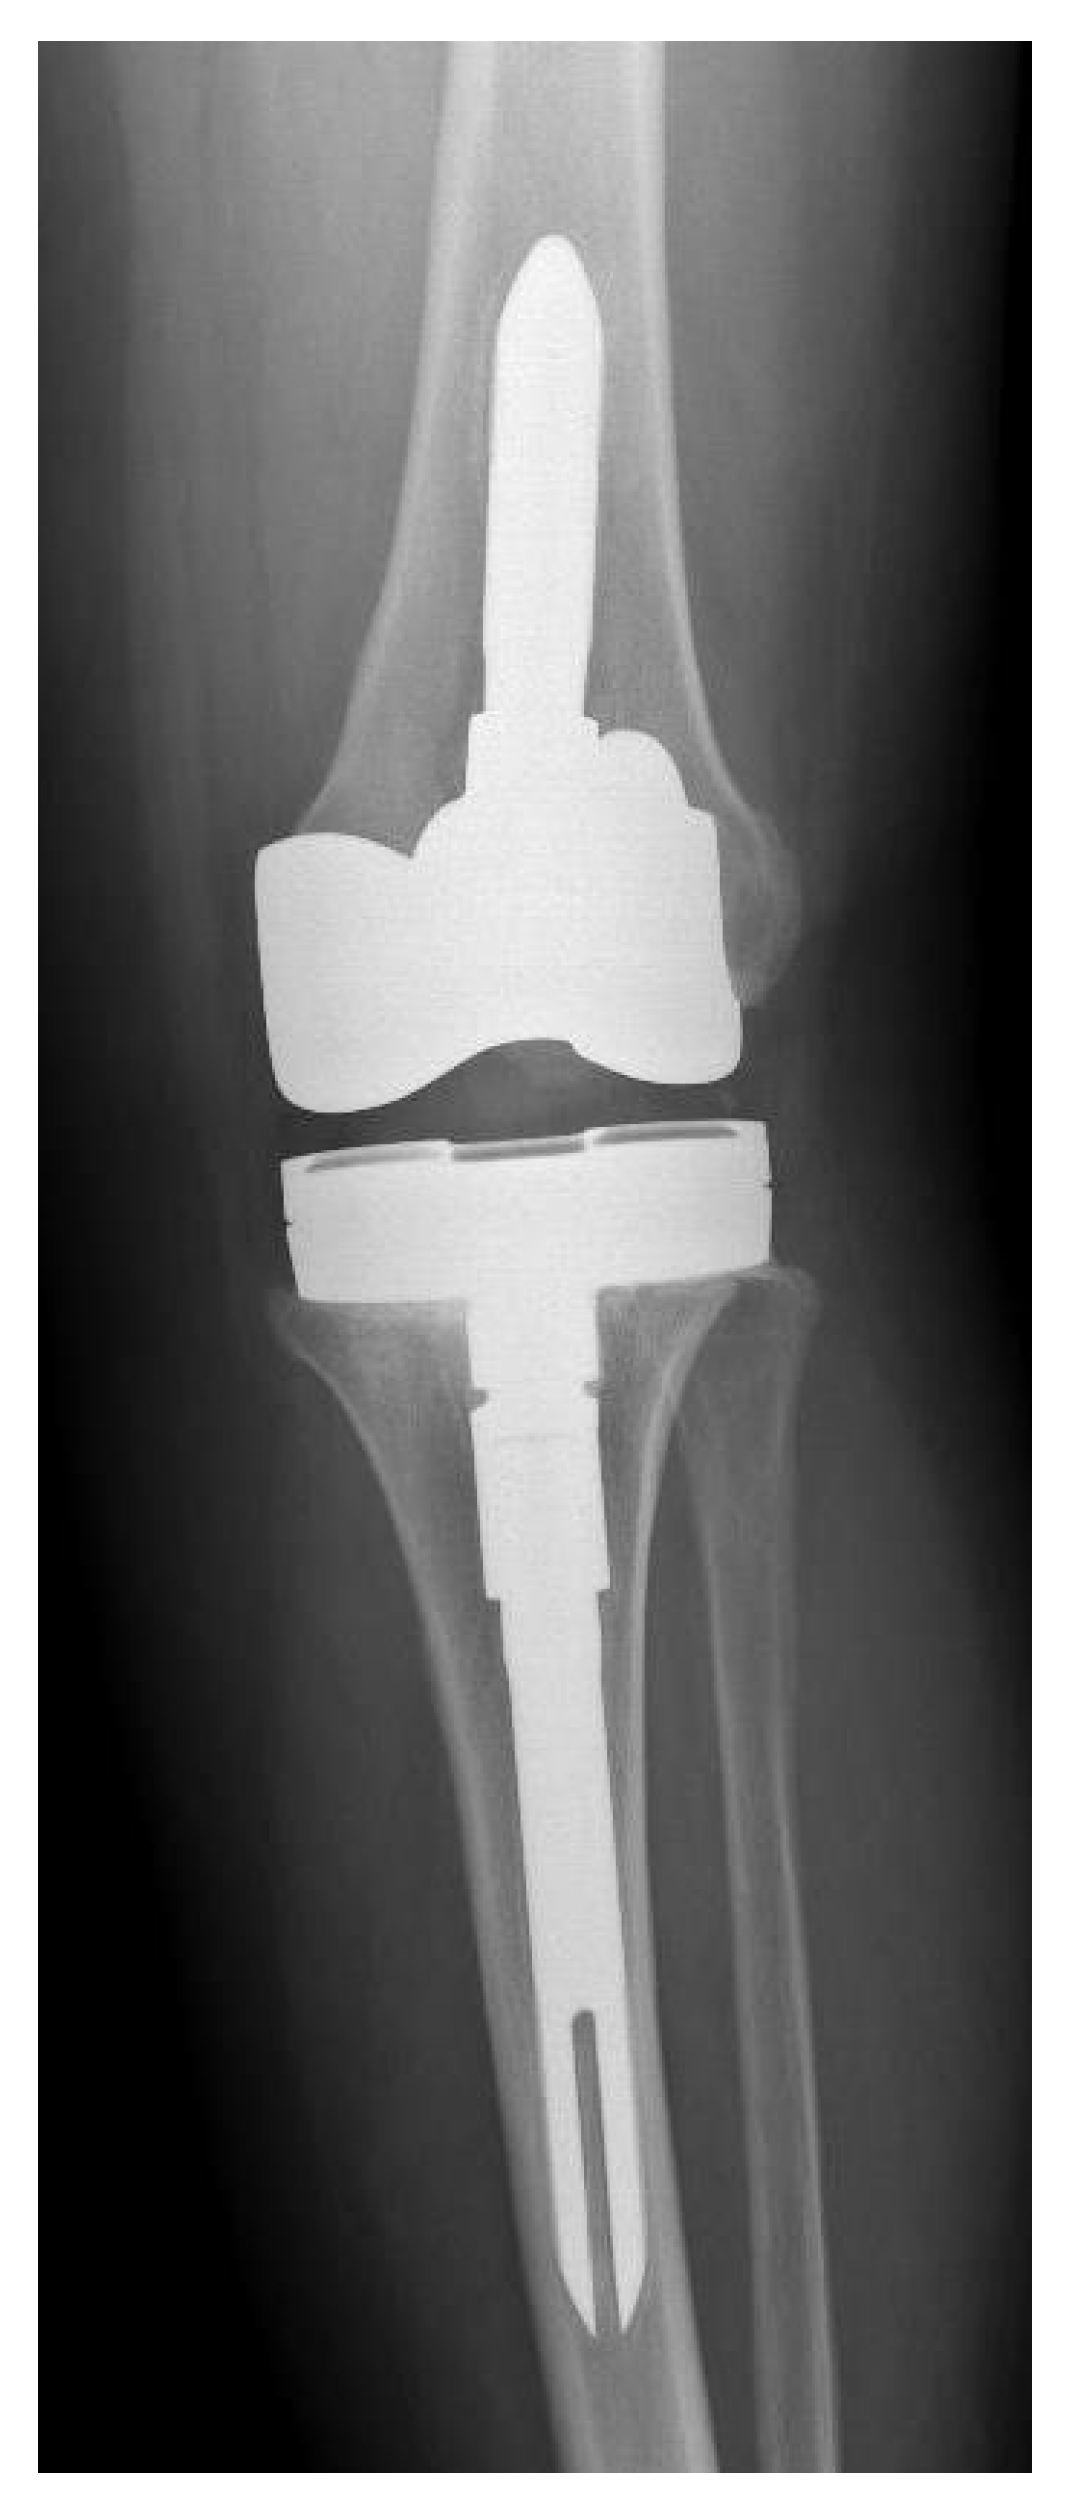

Figure 1.

Preoperative X-ray of knee joint with Streptococcus anginosus infection of patient number 5.

Figure 2.

Postoperative X-ray of new knee prosthesis of patient number 5.